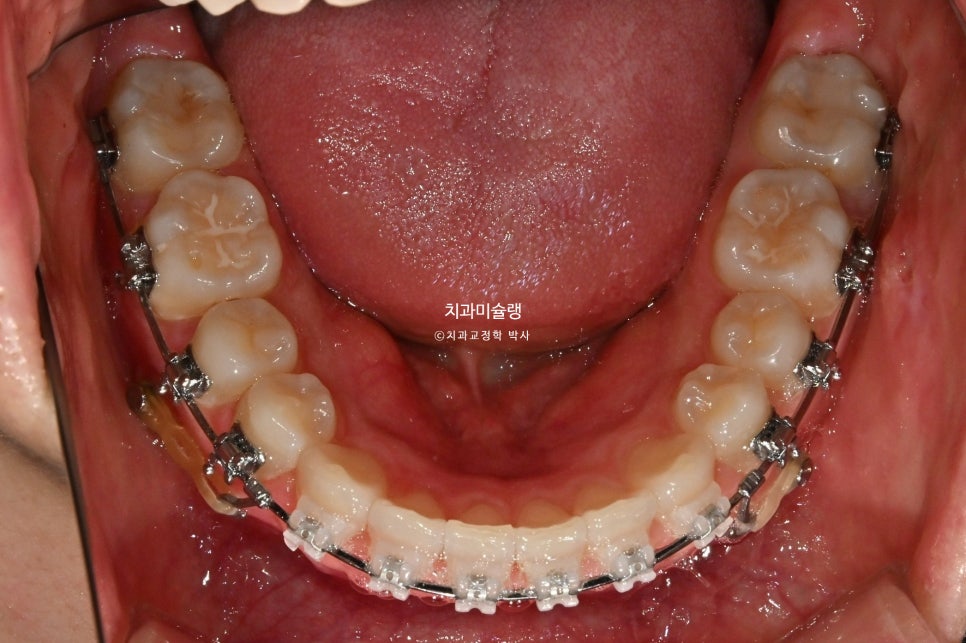

치료 시작 1년차 모습입니다. 치료 도중 턱관절 불편감은 딱히 없었습니다.

고정용 나사를 4군데 심고 전체치열을 뒤로 당기고 있습니다.